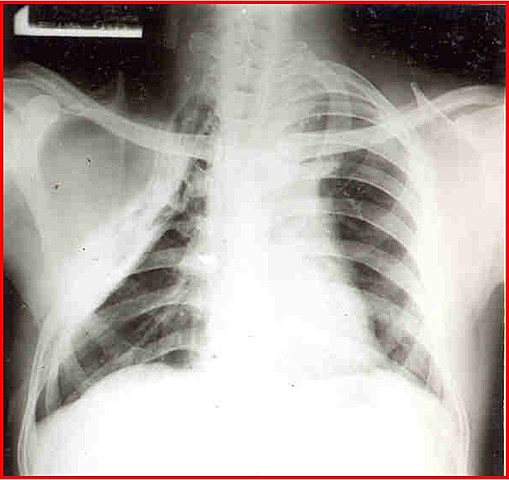

Tuberculosis

Enfermedad infecciosa y transmisible, aislamiento de la bacteria.